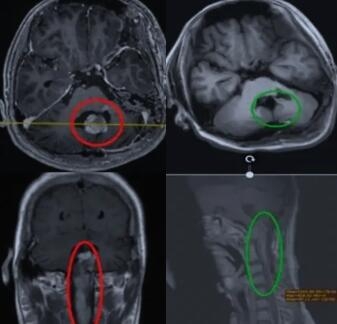

病灶多边界清楚、常见囊变、钙化及壁结节形成(图→),占位效应轻,一般无水肿或轻度水肿。CT 常见钙化,囊变,常呈结节状、环状、斑片状或点条状钙化,钙化为重要征象。MR 根据形态学可分为完全囊性,囊实性及实性。

(by Osborn Brain)

脑干-脊髓节细胞胶质瘤近全切手术

10+岁男孩,左手无力6年,辗转国内各大医院,考虑生长缓慢、而且手术难完全切除,会复发,进行保守观察。后肿瘤逐渐增大,从生命禁区“脑干”延伸到“颈髓”,肿瘤大小33*42*94mm,后于INC国际巴教授来华疑难手术示范行近全切手术。